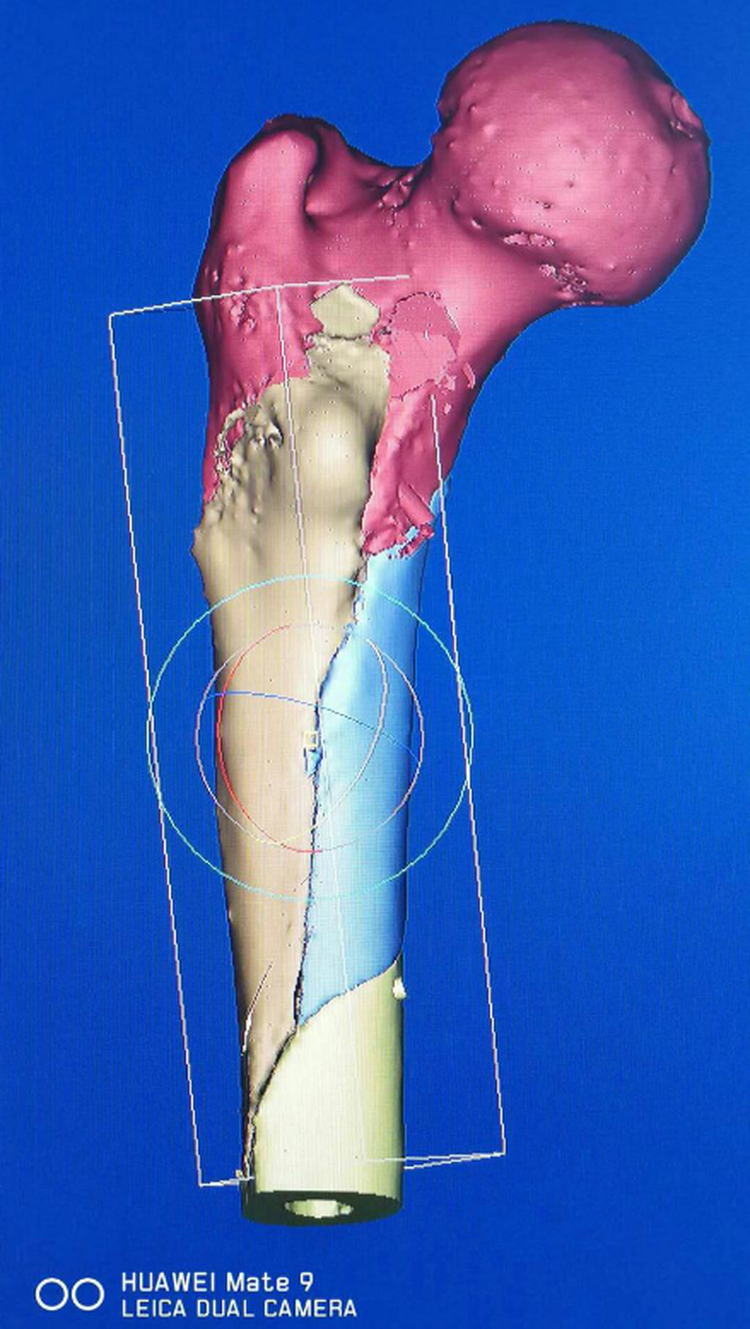

術(shù)前模擬預(yù)復(fù)位影像

我院骨創(chuàng)傷一科趙占富主任及其團隊近年將數(shù)字骨科應(yīng)用到臨床工作中,術(shù)前通過3D打印模型準(zhǔn)確判斷骨折類型,移位方向,對于手術(shù)方案的制定(手術(shù)入路的選擇,固定方式的選擇等)有很大幫助,數(shù)字骨科還能實現(xiàn)術(shù)前精確復(fù)位,導(dǎo)板設(shè)計進釘通道,能有效實現(xiàn)精準(zhǔn)置釘,減少神經(jīng)血管損傷等并發(fā)癥的發(fā)生。